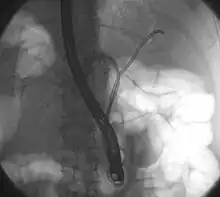

| Klatskin tumor during ERCP. Wires were inserted into the left and right biliary systems. Both parts were injected through a tube with contrast, but there is no contrast visible in the area of confluence of the two systems | |

Klatskin tumor, also known as hilar cholangiocarcinoma, is a type of cancer of the biliary tree (cholangiocarcinoma) occurring where the right and left bile ducts join.